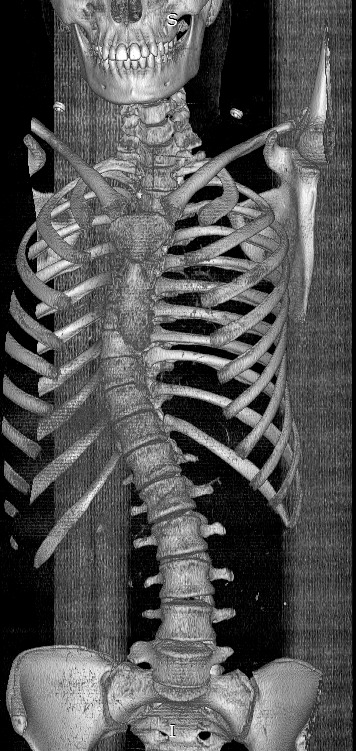

Figure 1.

Three-dimensional reconstructed computed tomography imaging (A) of whole spine of 18-year-old female patient with 11 thoracic vertebrae.

Figure 2.

Posteroanterior and lateral whole spine x-ray of 18-year-old female patient with 11 thoracic vertebrae.